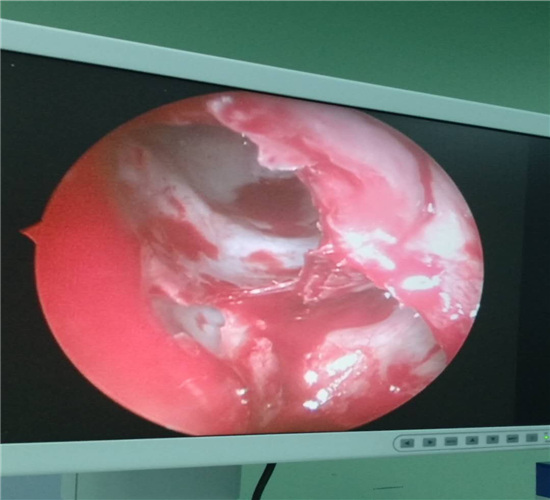

2019年4月15日何丕副主任医师、向庆勇主治医师、陈茂强主治医师、王超医师在全麻下为患者进行了经鼻鼻颅贯通性占位切除及一期前颅底缺损修复。